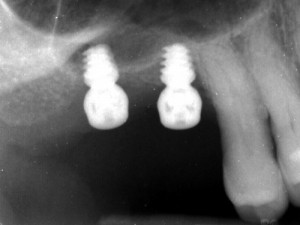

Recent advances in dental implants have led to an increase in the number of patients treated, with survival rates of more than 95% in a healthy population. ...